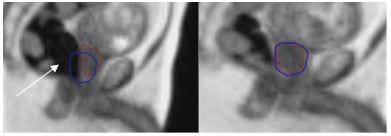

Movement of the prostate during treatment delivery due to rectal gas.

A B

C D

A Treatment is delivered when prostate (red contour) is contained within a tightly defined treatment margin (blue contour).

B and C Gas (or wind, white arrow) passing through the rectum, moved the prostate (red contour) out of the defined treatment margin (blue contour), ‘pausing’ treatment.

D Once the gas had passed, the treatment resumed as the prostate moved back into the treatment margin.